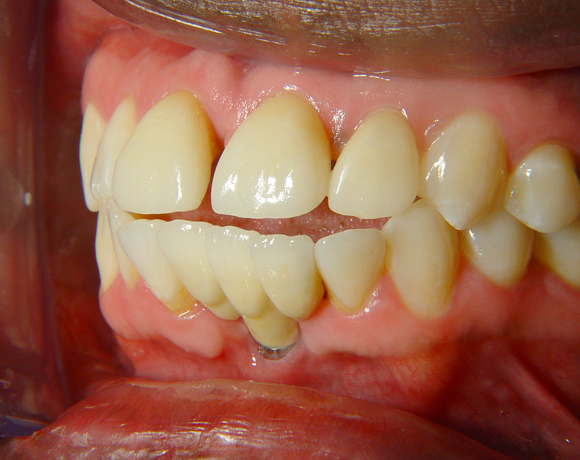

Diese Frontzahnsituation stellte den Behandler vor größere Probleme

Durch Abrasion der Seitenzähne wurden die Frontzähne nach labial verdrängt und lückig. Nach Verlust des Zahnes 41 entstand eine Lücke in der drei Zähne Platz fanden. Auch im Oberkiefer wurden die lateralen Lücken mit Veneers verkleinert.